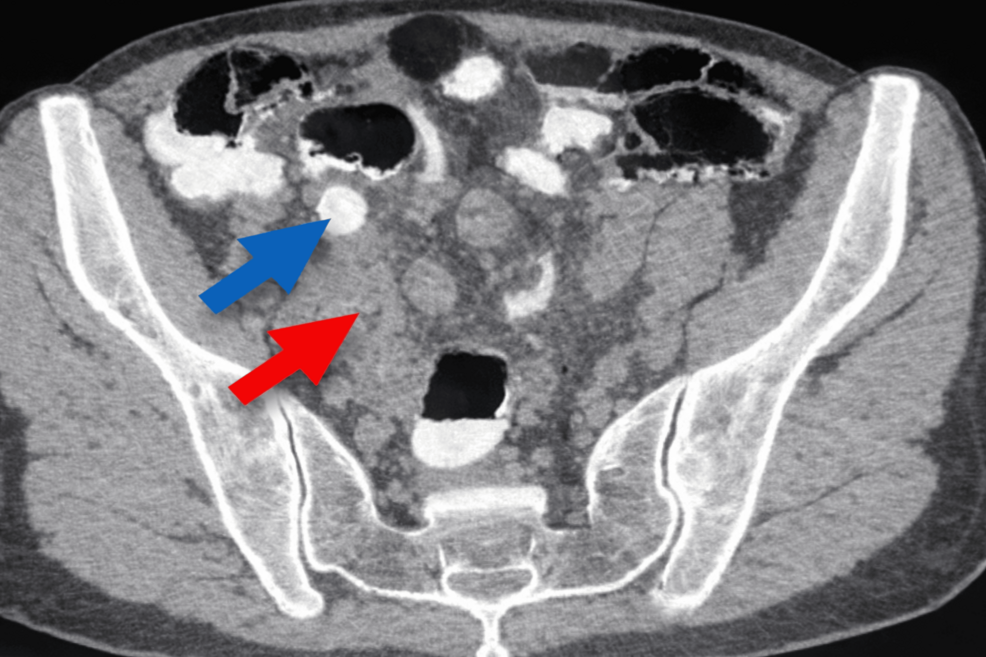

When a patient presents with these symptoms, clinicians must act quickly to avoid perforation. The gold standard for diagnosis remains imaging, specifically Computed Tomography (CT) scans or ultrasound. A CT scan is particularly effective at visualizing the diameter of the appendix and the presence of periappendiceal fat stranding, which indicates active inflammation.